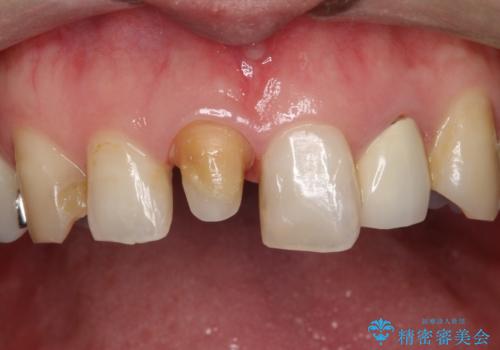

- 他院で装着された保険の前歯のかぶせ物が、他と歯と馴染まないので、自然な歯にしたいとのことで来院されました。

右上の1番目の歯の保険のかぶせ物と金属の土台を、ファイバーコアとオールセラミックにて再補綴する計画としました。

形態も色調もまわりの歯とは、調和がとれておらず、目立っていました。